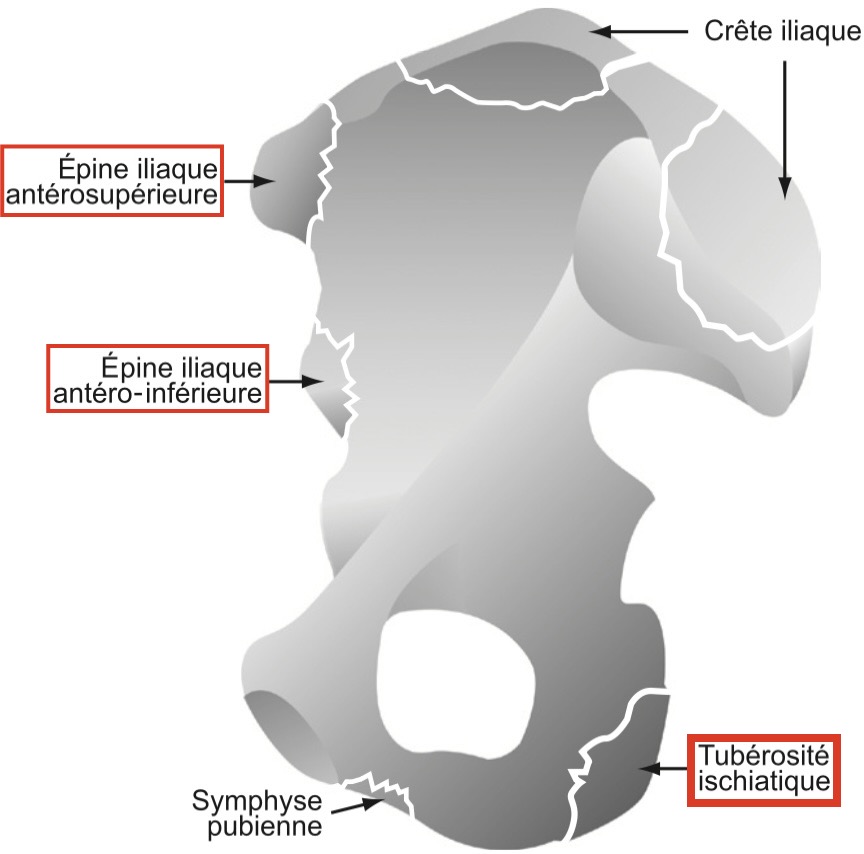

Avulsions apophysaires

Avulsions apophysaires